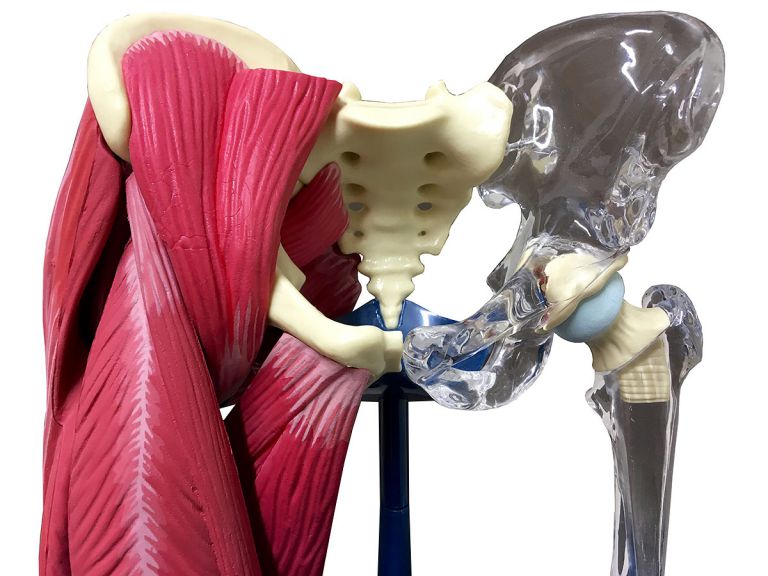

Эндопротезирование тазобедренного сустава: фото и схемы